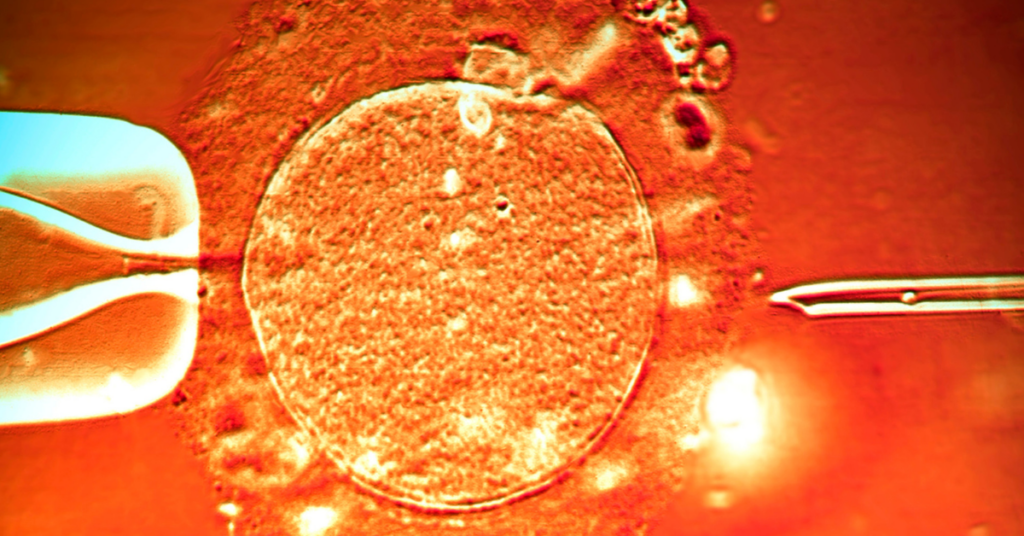

SUA sindrom, odnosno sindrom jedne pupčane arterije predstavlja određenu anomalliju koja nastaje u trudnoći. U pitanju je postojanje jedne pupčane arterije, umesto dve. Osim dve arterije, pupčana vrpca ima i jednu venu – kroz koju beba dobija sve što joj je potrebno od mame kako bi napredovala.

Sidrom jedne pupčane arterije znači da od bebe umesto kroz dve, samo kroz jednu arteriju otiče krv – što ne mora nužno predstavljati problem u razvoju fetusa. Ipak, preporučuju se češći pregledi i više potrebni analiza tokom trudnoće kako bi se pratilo stanje i bebe i mame.

Ukoliko se ultrazvukom utvrdi da postoji SUA sindrom dalji tok pregleda uključuje Dopler pregled krvnih sudova, odnosno pregled kojim se uz pomoć ultrazvučnih talasa prati protok krvi kroz različita tkiva bebe. Na ovaj način pregleda se i protok kroz krvi kroz pupčanu arteriju.